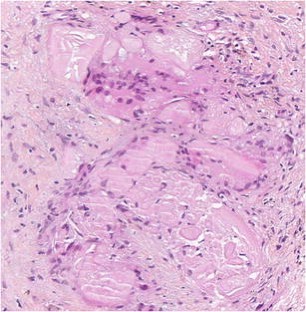

Low-risk prostate adenocarcinoma is classically managed either with active surveillance or radical therapy (such as external radiotherapy or radical prostatectomy), but both have significant side effects. Vascular-targeted photodynamic therapy (VTP) is a focal therapy proposed as an alternative approach for localized, low-volume, and low-Gleason score (≤6) carcinomas. We report histological modifications observed in prostate biopsies of 56 patients, performed 6 months after VTP using the photosensitizer TOOKAD® Soluble (WST11) and low-energy laser administered in the tumor area transperineally by optic fibers. In 53 patients, we observed sharply demarcated hyaline fibrotic scars, with or without rare atrophic glands, sometimes reduced to corpora amylacea surrounded by giant multinuclear macrophages. Mild chronic inflammation, hemosiderin, and coagulative necrosis were also observed. When residual cancer was present in a treated lobe (17 patients), it was always located outside the scar, most often close to the prostate capsule, and it showed no therapy-related modification. Histopathological interpretation of post-WST11 VTP prostate biopsies was straightforward, in contrast with that of prostate biopsies after radio or hormonal therapy, which introduces lesions difficult to interpret. VTP resulted in complete ablation of cancer in the targeted area.